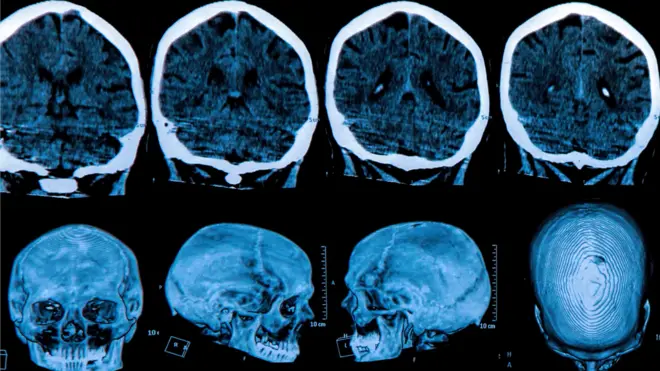

Este se infunde profundamente en el cerebro utilizando una resonancia magnética en tiempo real para guiar un microcatéter hasta dos regiones del cerebro: el núcleo caudado y el putamen. Esto requiere entre 12 y 18 horas de neurocirugía.

Fuente de la imagen, UCLH